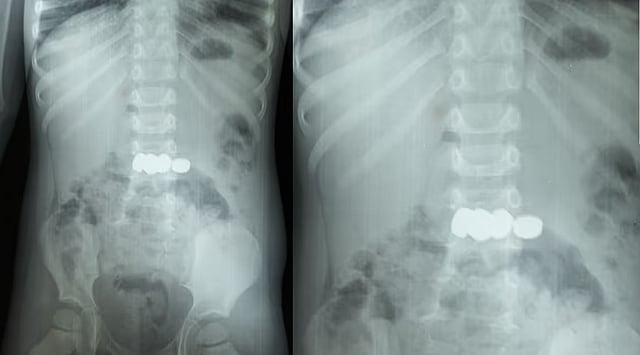

മേപ്പാടി: കളിക്കുന്നതിനിടെ അബദ്ധത്തിൽ അഞ്ച് ബാറ്ററികൾ വിഴുങ്ങിയ രണ്ട് വയസ്സുകാരനെ സങ്കീർണ്ണമായ എൻഡോസ്കോപ്പിയിലൂടെ ഡോക്ടർമാർ രക്ഷപ്പെടുത്തി. ബത്തേരി മൂലങ്കാവ് സ്വദേശികളായ ദമ്പതികളുടെ മകനാണ് അത്ഭുതകരമായി രക്ഷപ്പെട്ടത്. കുട്ടി ബാറ്ററികൾ വിഴുങ്ങുന്നത് ശ്രദ്ധയിൽപ്പെട്ട വീട്ടുകാർ ഉടൻ തന്നെ മെഡിക്കൽ കോളേജിൽ എത്തിച്ചത് വലിയ അപകടം ഒഴിവാക്കി.

ഗാസ്ട്രോ എന്ററോളജി വിഭാഗം സ്പെഷ്യലിസ്റ്റ് ഡോ. സൂര്യനാരായണന്റെ നേതൃത്വത്തിലാണ് ചികിത്സ ആരംഭിച്ചത്. ശസ്ത്രക്രിയ ഒഴിവാക്കി എൻഡോസ്കോപ്പിയിലൂടെ അഞ്ച് ബാറ്ററികളും സുരക്ഷിതമായി പുറത്തെടുത്തു. ഡോ. അഖിൽ, ഡോ. അഞ്ജന എന്നിവരും ദൗത്യത്തിൽ പങ്കാളികളായി.